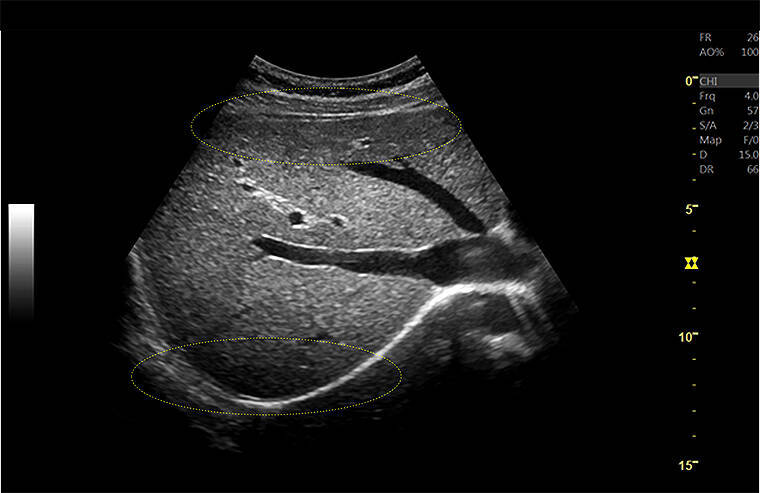

フルフォーカスにより浅部も深部も明瞭に描出、高いフレームレート

(LOGIQ Fortis)

近位部から深部にいたるまで、均一なイメージを把握できるよう、全視野・全深度フルフォーカスを実現した。

従来装置では、フォーカス近傍が明瞭に描出されているが、フォーカス以外の部分は明瞭に描出できず、関心領域に応じてフォーカスの位置を適宜変更する必要があった。

今回リリースされた「LOGIQ Fortis」では、フルフォーカスにより浅部も深部も明瞭に描出され、フレームレートも高いことがわかる。